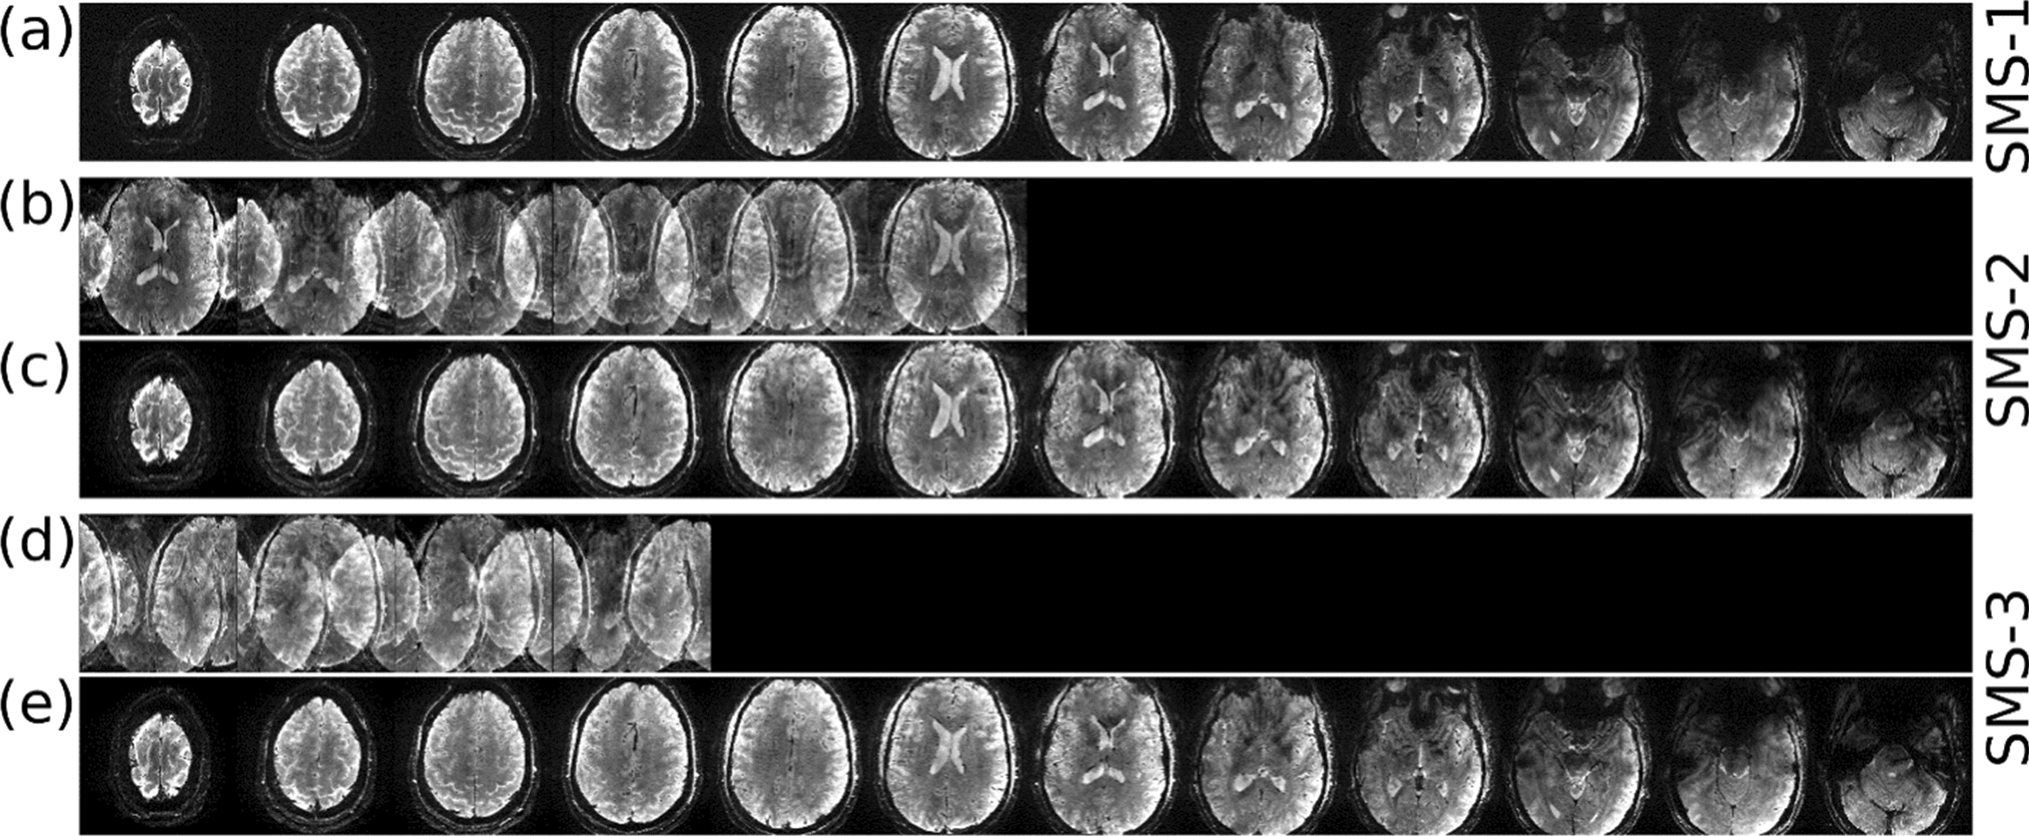

where Nsms is the SMS acceleration factor, \({{f}_{{\mathrm{sinc}_{l}}}}\) is the l-th time point of the single band sinc waveform, bijk is the complex RF scaling factor of the j-th transmit channel and k-th subpulse for the i-th slice in the SMS group, G is the amplitude of the slice-selective gradient, \(\Delta t\) is the RF dwell time, zi is the slice position of the i-th slice in the SMS group, and \({\phi }_{i}\) is an extra slice-dependent phase term that can be used to minimise the peak amplitude of the final multi-band waveform [49, 50]. The slice-dependent phase shift in bipolar spokes mentioned above can be absorbed into bijk when forming the multi-band pulse using this equation. Figure 2 shows an example of SMS GE images from [31] with the following imaging parameters: TR = 400 ms, TE = 14 ms, flip angle = 17 degrees, slice thickness = 1 mm, number of slices = 12, in-plane resolution = 0.28 × 0.28 mm2, matrix size = 562 × 562 × 12, bandwidth = 70 Hz/pixel, CAIPIRINHA slice shift [51] by gradient blip = FOV/2 for SMS-2 and FOV/3 for SMS-3, no in-plane GRAPPA acceleration. The total acquisition times for the single-band, SMS-2, and SMS-3 protocols were 3:44, 1:52 and 1:15 min, respectively.

Fig. 2

In vivo high-resolution SMS-GE images from [31] acquired with 3-spoke a single-band, b, c SMS-2 and d, e SMS-3 excitations. Rows b and d show the SMS images before slice-GRAPPA reconstructionṣ